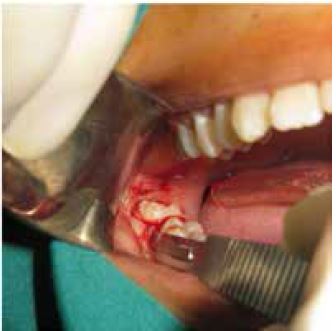

Seguidamente se realizó incisión en L con mango de bisturí N° 5 y hoja de bisturí N° 15; se procede al decolaje con legra apartando la mucosa y el periostio del hueso, para permitir una correcta visualización del campo operatorio (figura 3).